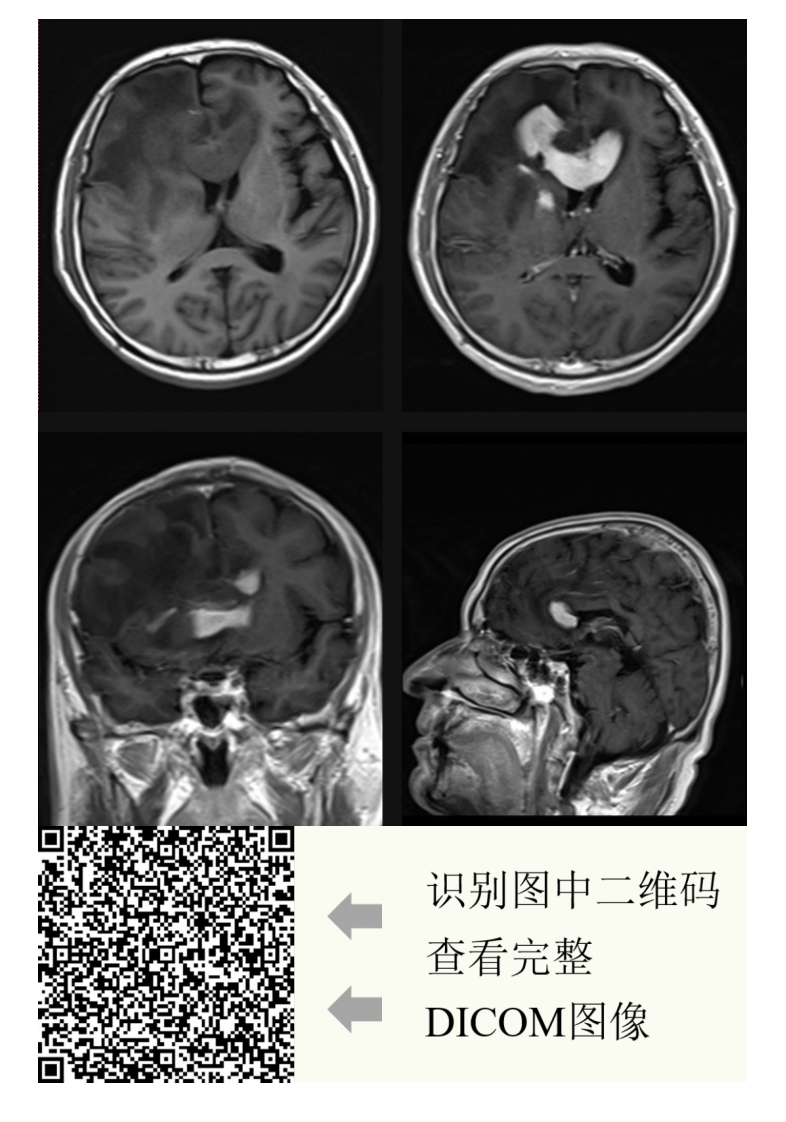

中大放射

20210608_2【晨读结果公布】2021.06.07神经系统疾病——病例1:间变型少突胶质细胞瘤;病例2:PCNSL;病例3:胼胝体急性梗死.pdf